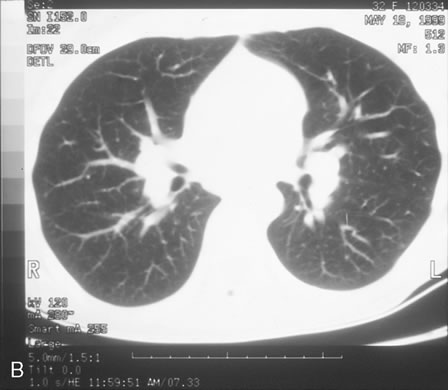

Pneumocystis carinii pneumonia once was the most common presentation of AIDS. It is typically of insidious onset, with features including dry cough, dyspnea, and a diffuse bilateral interstitial infiltrate evident on a chest roentgenogram. Typical multifocal fundus lesions have been described. They are yellow-white and have a characteristic pattern on fluorescein angiography (Fig. 10A, 10B, and 10C). Diagnosis is made by demonstrating the protozoon via sputum induction, bronchioalveolar lavage, and transbronchial or open-lung biopsies. Treatment modalities include trimethoprim-sulfamethoxazole (TMP-SMX).31

Fig. 10. A. The retinal involvement of Pneumocystis carinii is manifested by multifocal, yellow-white lesions. B and C. On fluorescein angiography, the lesions fail to delineate in the early phase (B) but stain in the late phase (C).